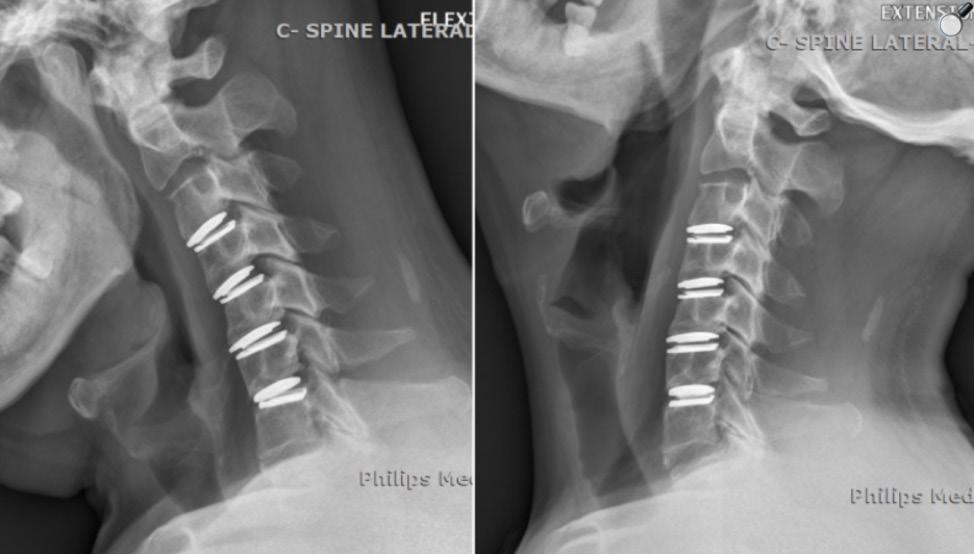

representing a 45.9% improvement and mirroring the success rates seen in 1- and 2-level trials. A 20-point visual analog scale (VAS) score for neck pain decreased by 49.4% (15.6 to 7.9) and for arm pain decreased by 54.1% (12.2 to 5.6). Improvements were noted as early as 6 weeks and were maintained through the 7-year follow-up. The rate of secondary surgery was remarkably low (3.6% for 3-level, 0% for 4-level), suggesting a favorable effect on adjacent segments. Long-term satisfaction was high (>88% at 7 years) (Figure).

In the previously mentioned series by Chang et al on 3-CDR vs ACDF, both pro -

Figure. Flexion and extension of lateral cervical radiographs obtained 2 years after multilevel cervical disc replacement showcasing preserved segmental motion and stability in implanted devices. Reproduced from Chang HK, Chang CC, Tu TH, et al. Four-level cervical disc arthroplasty. Int J Spine Surg. 2024;18(5):514520. Figure 2. doi:10.14444/8603.

cedures offered statistically significant and equivalent improvements in clinical symptoms (VAS, NDI, modified Japanese Orthopaedic Association scores), despite the drastic differences in ROM outcomes.1 Similarly, their later series on 4-CDR yielded significant improvements in all clinical metrics (NDI, VAS) without any reported reoperations. 2 The follow-up periods for these studies were approximately 34 months.